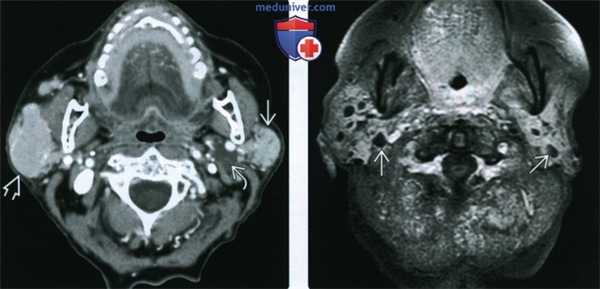

(Слева) На аксиальной КТ с КУ определяются признаки СШ с поражением обеих поднижнечелюстных желез, имеющих неоднородную, «пятнистую» структуру. Правая железа слегка увеличена.

(Справа) На аксиальной КТ с КУ определяется выраженная неоднородность структуры околоушных желез, выглядящих патологически измененными, с наличием мягкотканного компонента, разделенного областями, выглядящими более кистозными. Также визуализируются небольшие кальцинаты.

(Слева) КТ с КУ, аксиальная проекция. Отмечается интенсивное накопление контраста в обеих околоушных железах, имеются участки кистозной дегенерации. В правой околоушной железе обнаруживается солидное образование, равномерно накапливающее контраст, которое представляет собой лимфому. У пациентов с синдромом Шегрена повышен риск возникновения околоушных лимфом. При обнаружении любого солидного образования требуется выполнение биопсии.

(Справа) МРТ Т1ВИ FS с КУ, аксиальная проекция. Множественные кисты в обеих околоушных железах. Вокруг каждой из них имеется тонкое кольцо накопления контраста, что весьма характерно для синдрома Шегрена.